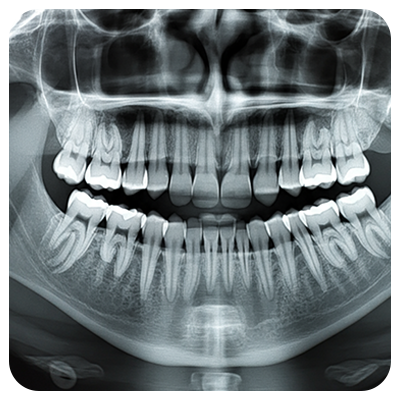

junio 5, 2019La cefalometría es una técnica de gran utilidad en odontología y especialmente en la ortodoncia, ya que permite obtener medidas del cráneo a partir de radiografías que luego se calcan sobre un acetato para establecer los puntos anatómicos más significativos y medir las distancias y relaciones entre unos y otros (huesos, músculos, dientes, etc.) atendiendo a diferentes criterios para luego compararlos con los patrones de normalidad.

Es por esta razón que la cefalometría es un procedimiento diagnóstico fundamental antes de iniciar cualquier tratamiento ortodóncico, ya que permite determinar las anomalías morfológicas, de colocación y de crecimiento de los dientes, para así establecer el objetivo del tratamiento y poder realizar el adecuado seguimiento del mismo.